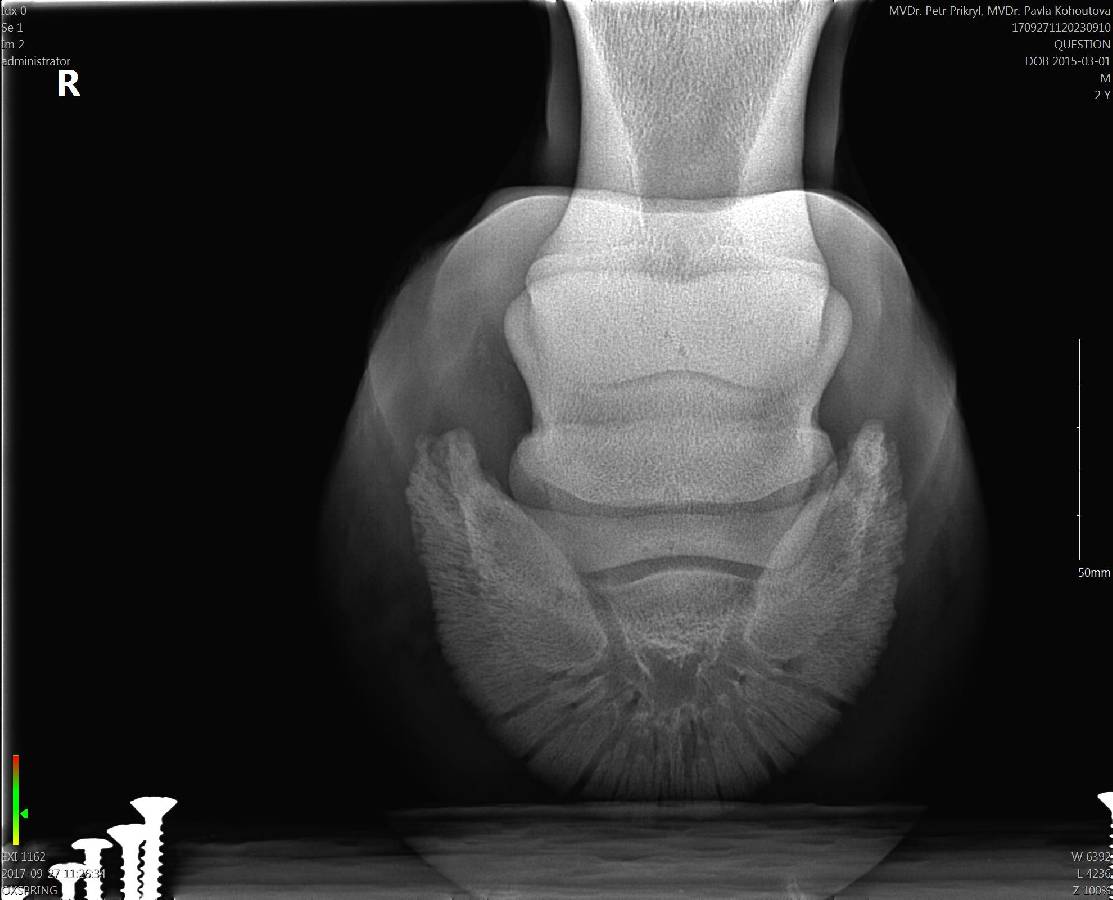

O zdravotním stavu dále vypovídají přiložené rentgenové snímky

Pod textem ke stažení dokument  Základní informace o koni + rodokmen + fotogalerie + rentgenová dokumentace